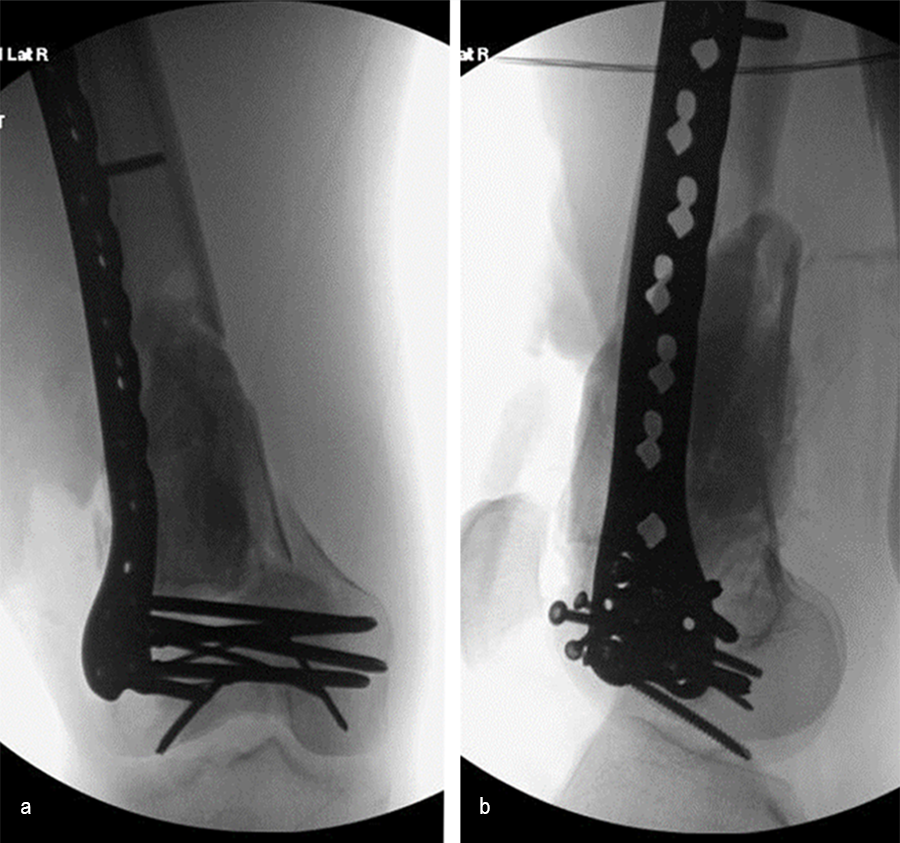

At 5 days post-initial surgery, the lung injury was improved, so the patient underwent open reduction and internal fixation (ORIF) of the right distal femur with resection of devitalized bone and cement spacer placement (Fig 7). Definitive fixation of the other fractures (ankle and ribs) was undertaken over time.

Following the advent of Covid-19 in early 2020, the patient was lost to follow-up for almost one year and was eventually seen again in December 2020 (Fig 8). At this follow-up, a CT scan was planned for the right distal femur and a graft cage ordered. Surgery was scheduled for early 2021.